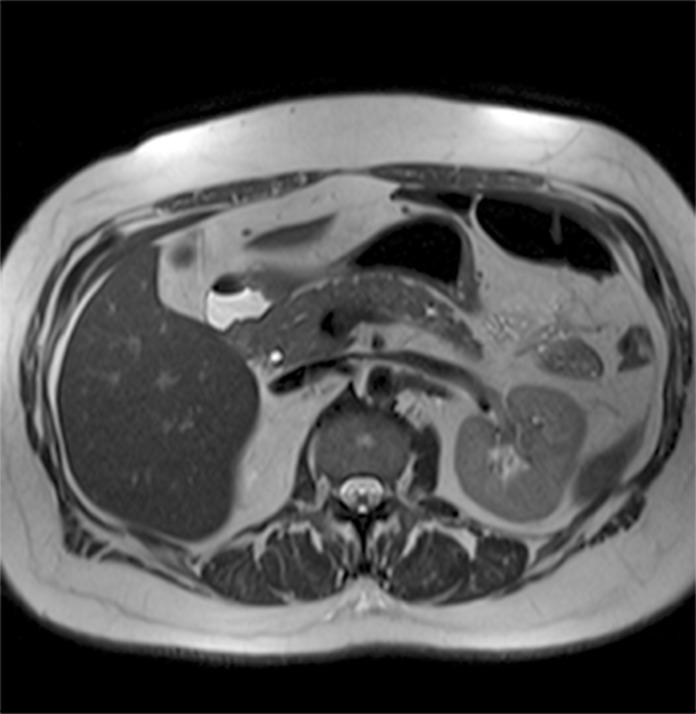

3特斯拉磁共振成像中偶然发现的胰腺囊肿的患病率

Prevalence of incidental pancreatic cysts on 3 tesla magnetic resonance.

To ascertain the prevalence of pancreatic cysts detected incidentally on 3-Tesla magnetic resonance imaging (MRI) of the abdomen and correlate this prevalence with patient age and gender; assess the number, location, and size of these lesions, as well as features suspicious for malignancy; and determine the prevalence of incidentally detected dilatation of the main pancreatic duct (MPD).

Retrospective analysis of 2,678 reports of patients who underwent abdominal MRI between January 2012 and June 2013. Patients with a known history of pancreatic conditions or surgery were excluded, and the remaining 2,583 reports were examined for the presence of pancreatic cysts, which was then correlated with patient age and gender. We also assessed whether cysts were solitary or multiple, as well as their location within the pancreatic parenchyma, size, and features suspicious for malignancy. Finally, we calculated the prevalence of incidental MPD dilatation, defined as MPD diameter ≥ 2.5 mm.

Pancreatic cysts were detected incidentally in 9.3% of patients (239/2,583). The prevalence of pancreatic cysts increased significantly with age (p<0.0001). There were no significant differences in prevalence between men and women (p=0.588). Most cysts were multiple (57.3%), distributed diffusely throughout the pancreas (41.8%), and 5 mm or larger (81.6%). In 12.1% of cases, cysts exhibited features suspicious for malignancy. Overall, 2.7% of subjects exhibited incidental MPD dilatation.

In this sample, the prevalence of pancreatic cysts detected incidentally on 3T MRI of the abdomen was 9.3%. Prevalence increased with age and was not associated with gender. The majority of cysts were multiple, diffusely distributed through the pancreatic parenchyma, and ≥ 5 mm in size; 12.1% were suspicious for malignancy. An estimated 2.7% of subjects had a dilated MPD.